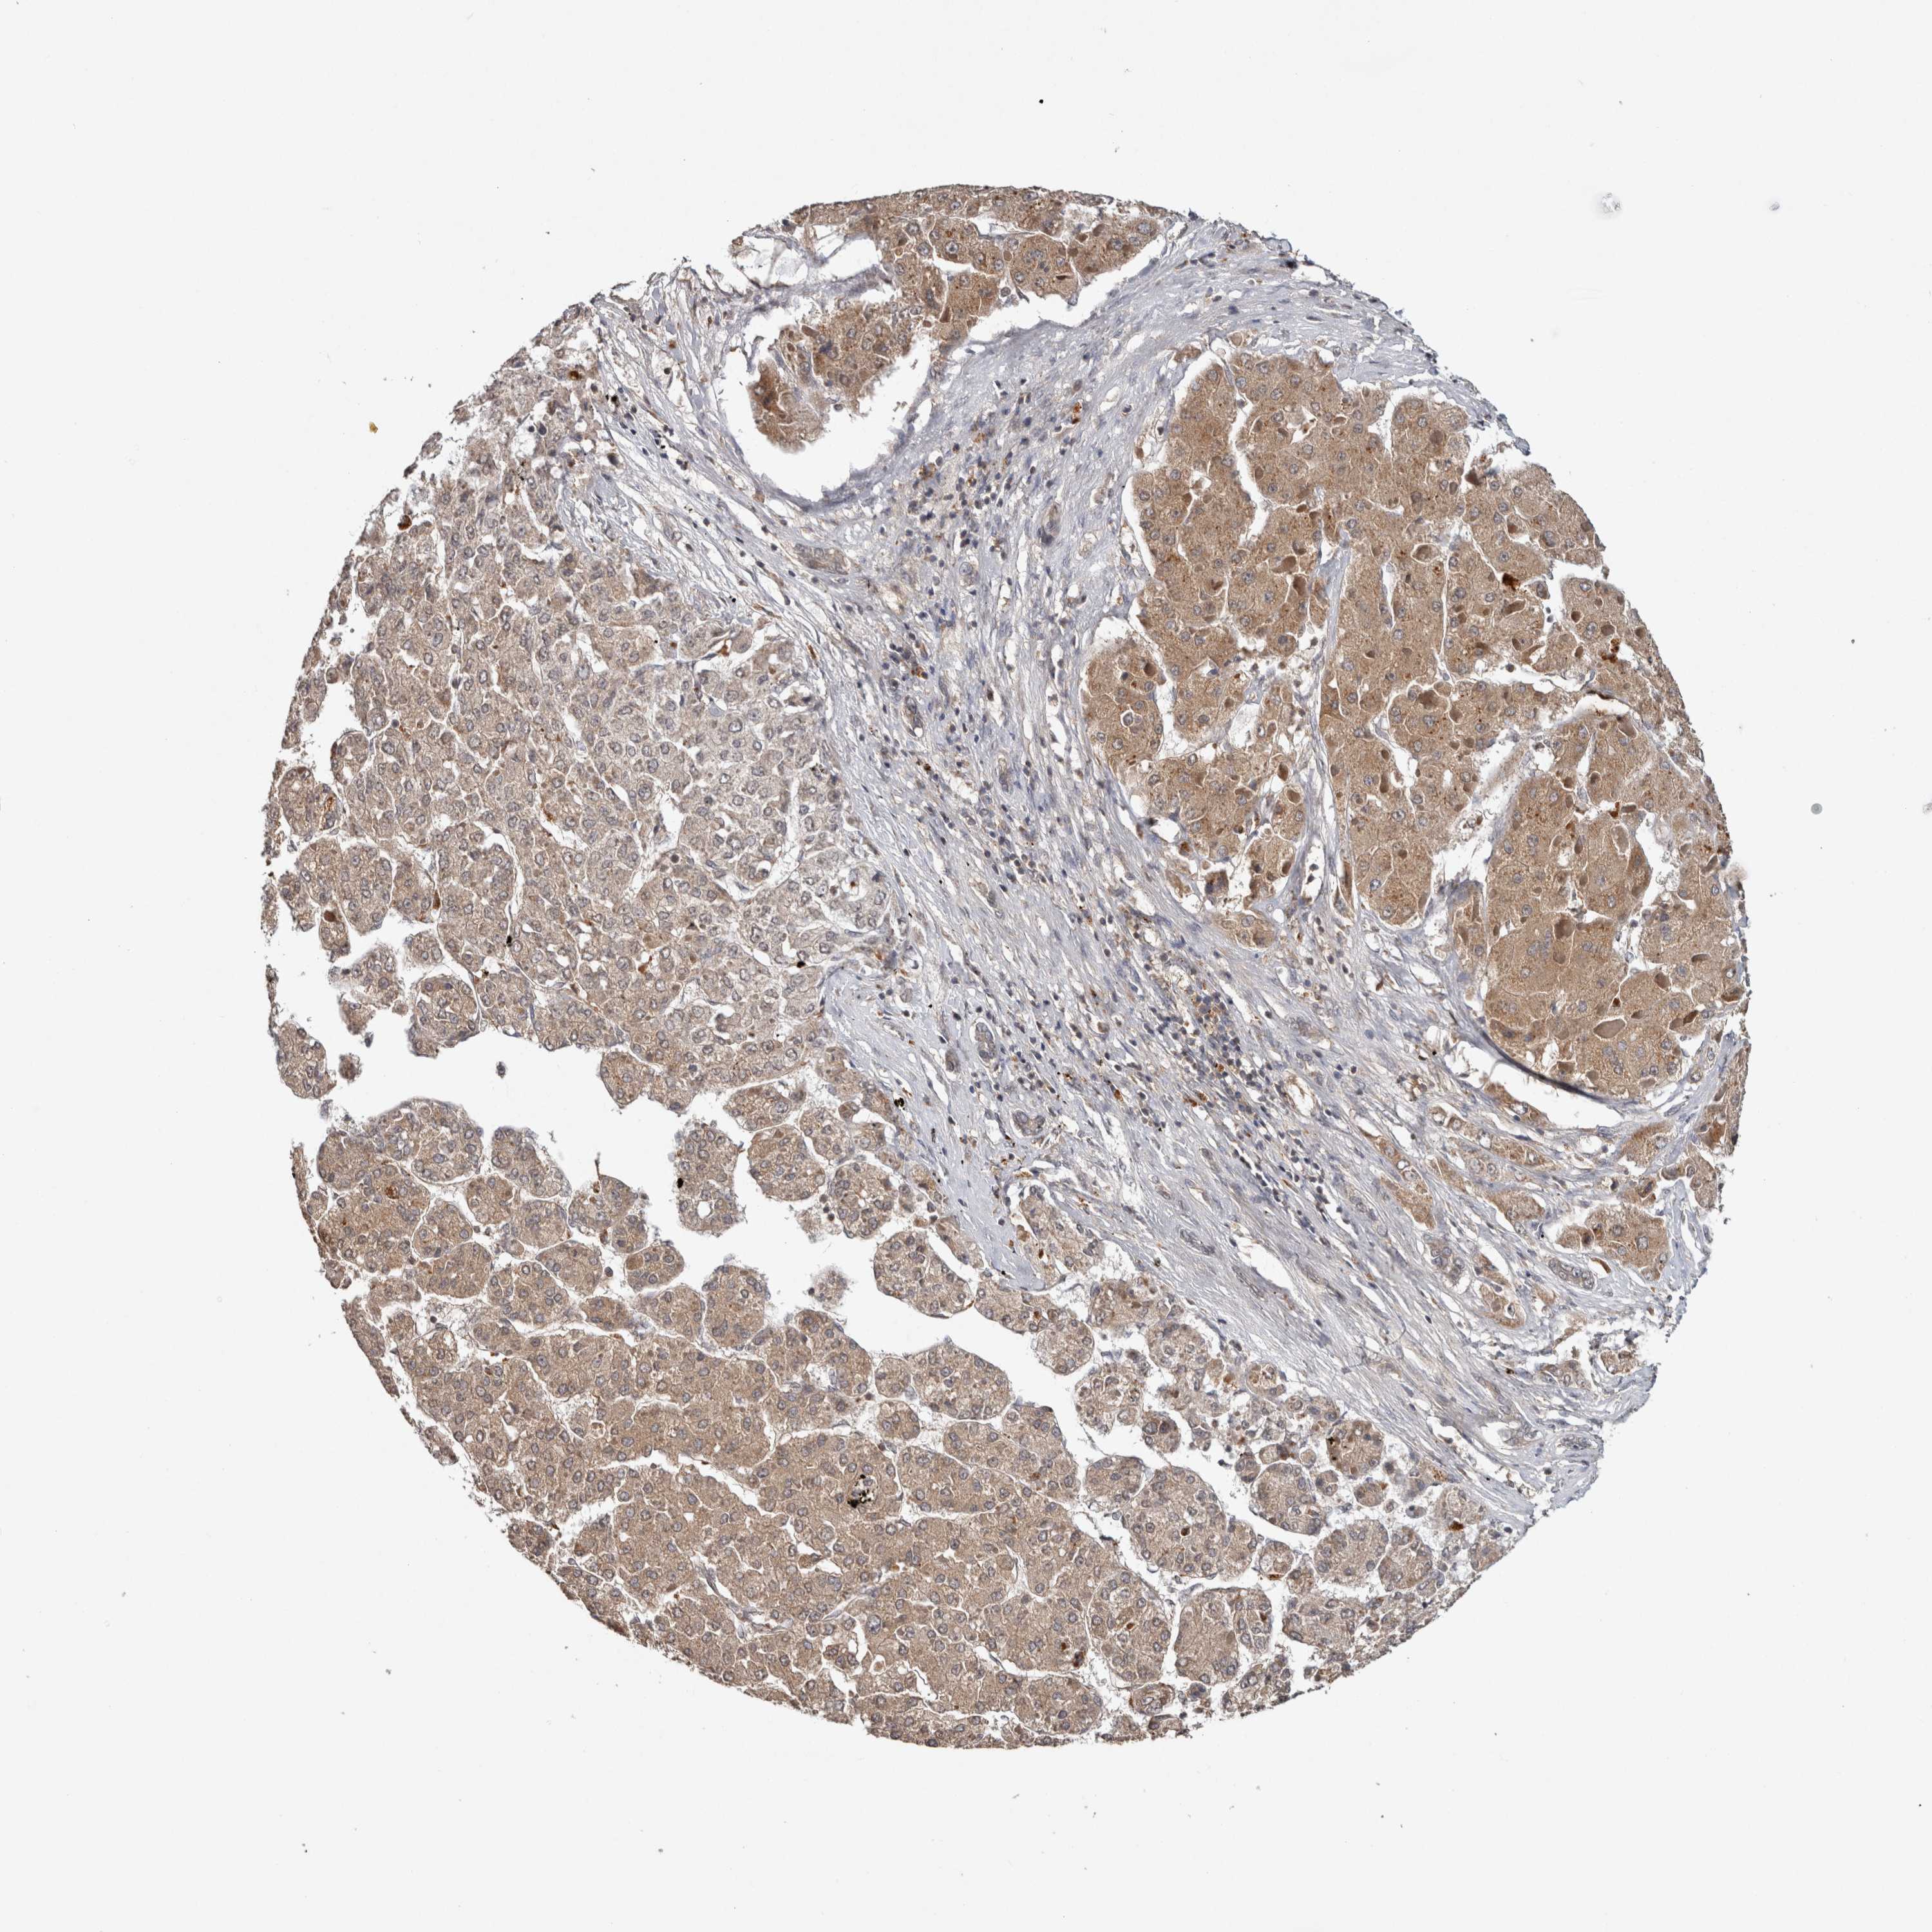

LIVER CANCER - Protein expressioni

A mouse-over function shows sample information and annotation data. Click on an image to view it in a full screen mode. Samples can be filtered based on level of antibody staining by selecting one or several of the following categories: high, medium, low and not detected. The assay and annotation is described here.

Note that samples used for immunohistochemistry by the Human Protein Atlas do not correspond to samples in the TCGA dataset.

Antibody stainingi

Antibody staining in the annotated cell types in the current human tissue is reported as not detected, low, medium, or high, based on conventional immunohistochemistry profiling in selected tissues. This score is based on the combination of the staining intensity and fraction of stained cells.

Each image is clickable and will lead to virtual microscopy that enables deeper exploration of all samples and also displays staining intensity scores, fraction scores and subcellular localization as well as patient and tissue information for each sample.

Antibody HPA040611

Antibody CAB025464

Staining

High

Medium

Low

Not detected

Intensity

Strong

Moderate

Weak

Negative

Quantity

>75%

75%-25%

<25%

None

Location

Nuclear

Cytoplasmic/membranous

Cytoplasmic/membranous,nuclear

Cholangiocarcinoma

Carcinoma, Hepatocellular, NOS